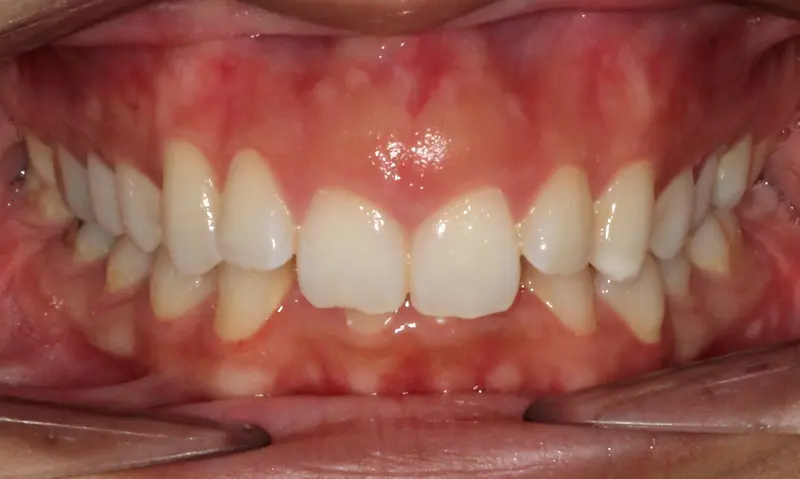

After treatment: The Extraction Myth

After

Before treatment: The Extraction Myth

Before

Bimaxillary protrusion (teeth flaring forward) causing lip incompetence. The patient struggled to close his lips comfortably, straining the chin muscle (mentalis).

A strategic extraction plan (4 premolars) allowed us to retract the front teeth. Note the dramatic improvement in chin projection and facial balance. The extractions did not flatten the face; they harmonized it.